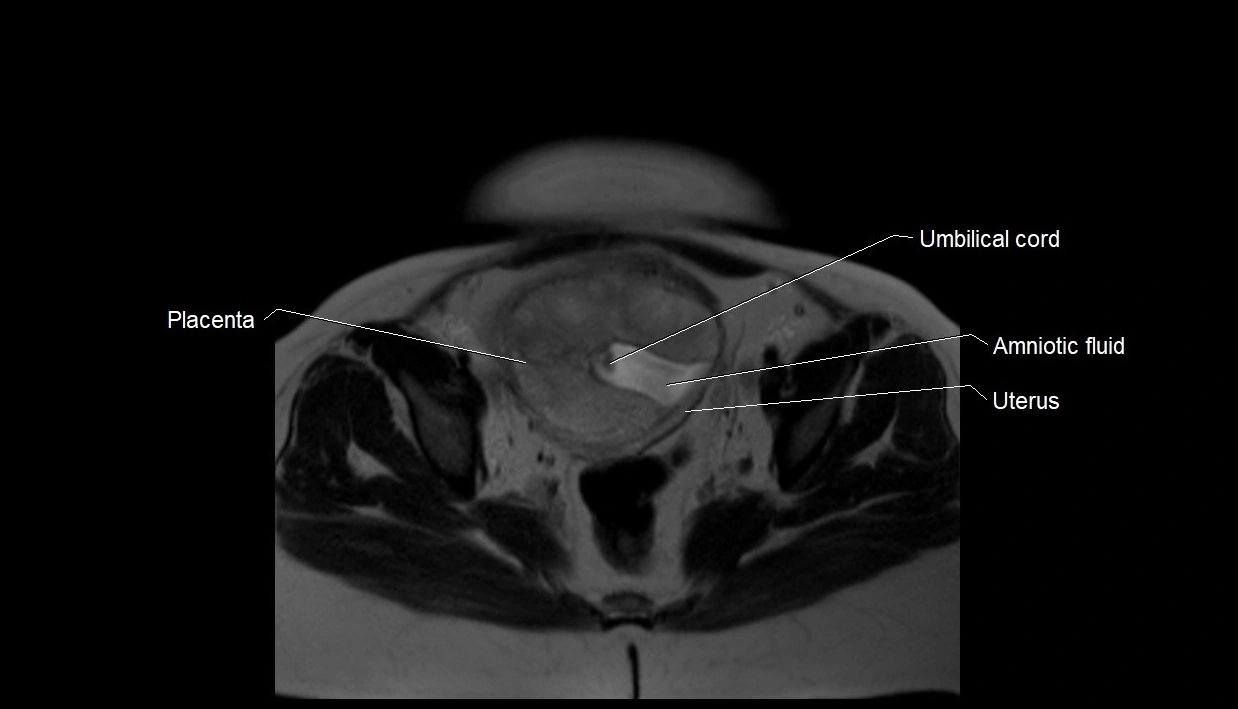

MRI Appearance

T2 HASTE (T2 GRE):

• Amniotic fluid shows very bright hyperintense signal

• Provides natural contrast against fetus and placenta

• Small particles (vernix) may appear as scattered hypointense foci within bright fluid

MRI image

image